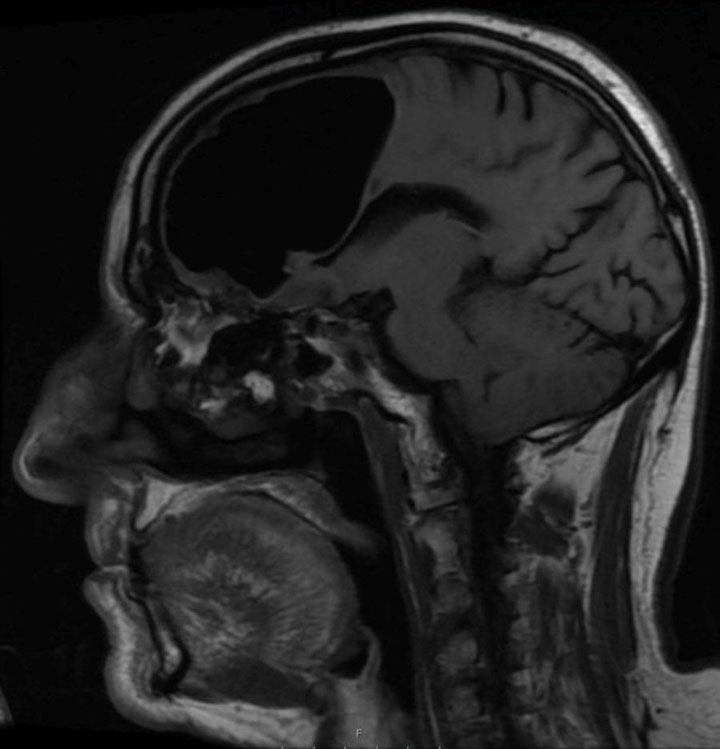

MRI showing the cavity in the man’s skull. BMJ Case Reports 2018

MRI showing area of acute infarction, or stroke. BMJ Case Reports 2018